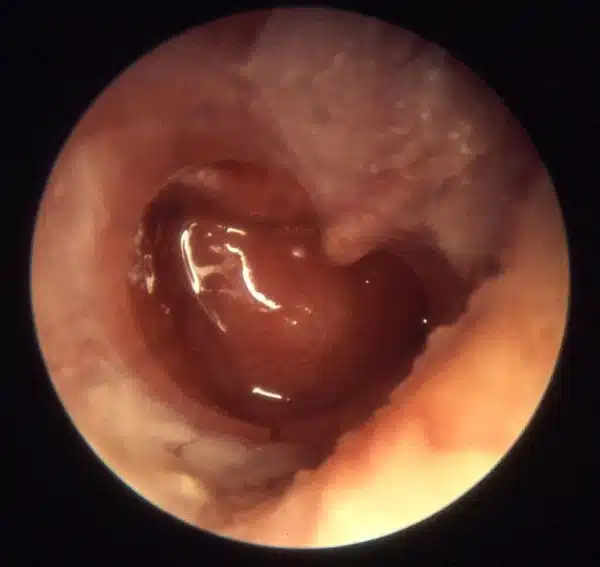

Bullous myringitis (type of AOM)

Can be mistaken for herpes zoster oticus (Ramsay Hunt)

The tympanic membrane shows erythematous changes with visible isolated hemorrhagic infiltrates (dark spots)